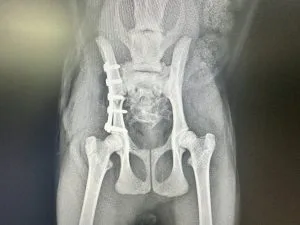

犬猫の骨盤骨折とは|プレート固定による整復と術後について解説

犬や猫の骨盤骨折とは、骨盤を構成する腸骨・恥骨・坐骨などが外傷で折れ、歩行や排泄機能に影響することもあります。今回はプレート固定による整復手術の実例をもとに、その流れと術後ケアをわかりやすく解説します。